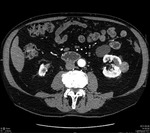

Proces zapalny obejmujący torbiel nerki może dać bardzo różnorodny obraz (zmiana charakteru płynu w obrębie torbieli znajduje odbicie w badaniach obrazowych). Obwodowe wzmocnienie pokontrastowe może wręcz potwierdzać występowanie ropnia.1 Tej koncepcji przeczy jednak stan kliniczny pacjenta i brak odchyleń od normy w badaniach laboratoryjnych. Rak nerkowokomórkowy przeważnie jest guzem o charakterze litym, jednak w ok. 20% przypadków może zawierać także elementy torbielowate.1 Obecność wzmocnienia obwodowego w fazie pokontrastowej badania TK, zwłaszcza rozmieszczonego nieregularnie, zawsze musi budzić podejrzenie rozrostu nowotworowego. U pacjenta, którego przypadek jest opisywany, na podstawie wyników badania histopatologicznego rozpoznano raka nerkowokomórkowego. Innym przykładem guza nowotworowego o charakterze torbielowatym, który może występować w obrębie nerki, jest torbielakogruczolak, znany także jako nerczak torbielowaty wielokomorowy. Guz najczęściej stwierdza się u małych chłopców i kobiet w wieku 40-70 lat (inaczej niż w prezentowanym przypadku). Składa się on z licznych torbieli wypełnionych śluzowatą treścią. W obrębie guza często występują zwapnienia (szacuje się, że w 10-50% przypadków), natomiast obszary krwotoczne lub martwicy, zazwyczaj obserwowane w rakach nerkowokomórkowych, w nerczakach torbielowatych są rzadkie. Kielichy i miedniczka nerki bywają modelowane przez torbiele, które nie komunikują się z układem wydalniczym. Po podaniu środka kontrastowego wzmocnieniu ulega lita część guza.1 Typowy obraz TK torbielakogruczolaka nerki zaprezentowano na rycinie 3A-C.